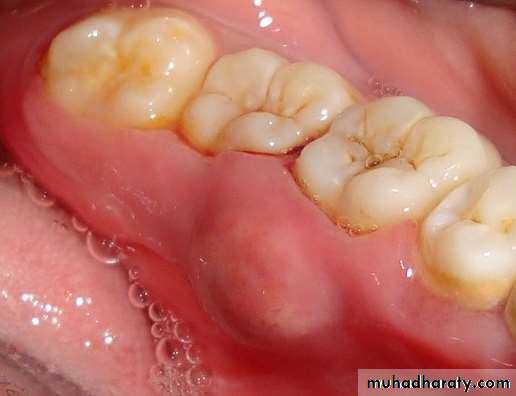

• Pericoronal abscess: Localized accumulation of pus within the overlying gingival flap surrounding the crown of an incompletely erupted tooth.

Pericoronitis

Clinical Features:

The partially erupted or impacted Mandibular third molar is the most common site. Maxillary Third molar, Mandibular First, Second Molars are also affected.

The space between the crown of the tooth and operculum (i.e. overlying gingival flap) harbours food debris and promotes bacterial growth due its relative inaccessibility to the cleansing measures.

The operculum, even in patients without any symptoms is chronically inflamed with ulcerations in the inner aspect.